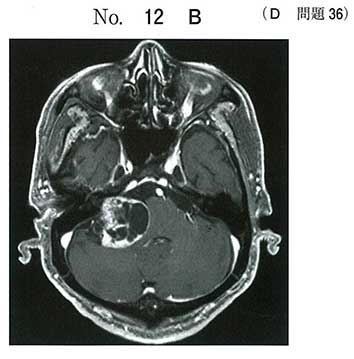

病理は神経鞘腫の典型像です。Antoni Aですね。でも何より、骨状件のCTで右内耳道の漏斗状拡大があり、増強画像で小脳橋角部の内耳道につながる腫瘍ですので、dを選択できないといけません。嚢胞性の神経鞘腫です。うちの学生はできただろうか・・・

まったく同じ病理図と小脳橋角病変の画像とセットで学内試験で見ていて助かりました。

その時もリング状エンハンスでaを選んだ人が圧倒的に多く、小脳橋角病変は神経鞘腫と髄膜腫を思い出すようしてたので助かりました。

病理でpalisadingとVerocay bodyを見せてます。

好酸性線維状胞体と桿状核を有する腫瘍細胞が束をなして増殖する神経鞘腫の像。

主訴と経過から聴神経腫瘍(神経鞘腫)かなと。画像から小脳橋角部腫瘍と言ったら髄膜腫か神経鞘腫。明らかに髄膜腫ではないから神経鞘腫。で選びました。病理所見は知りませんでした汗。国試テクのringを覚えるなら、小脳橋角部腫瘍もテクとして覚えとくといいでしょう。